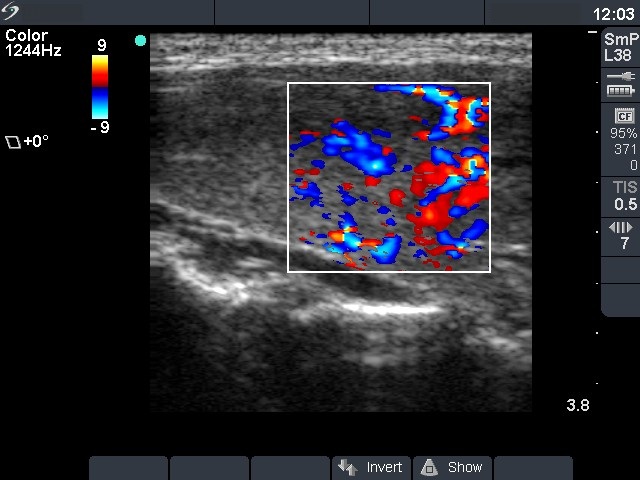

Graves' disease - Case 1049

Follow-up investigation 12 months after first visit (ultrasonographic picture 3)

Patient on daily 10 mg methimazole therapy in euthyroid state

Right lobe, longitudinal scan, color Doppler method. The vascularization is increased.